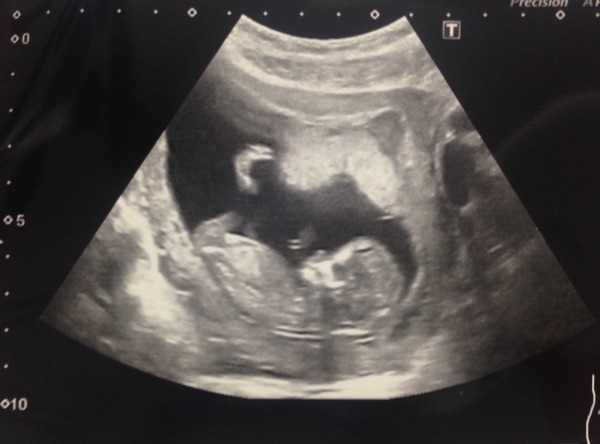

juniper i would have guessed boy - but a) i am guessing nd b) not sure i believe in skull theory. Here's my little she-Bean. She apparently has a girlie head! I need to find my scans from my boys - when i finally move into the new house i can dig them out - 9 days until we get the keys, 12 days until moving day Grin

I've posted this pic before but I just love showing the little fella off! I'm not sure I believe the skull theory as his skull looks very similar in shape to some of the pics that have been posted of girls?